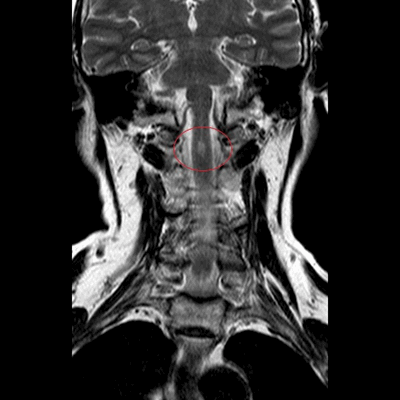

МРТ шеи: перелом зубовидного отростка, миелопатия (дисфункция спинного мозга в области поврежденных шейных позвонков) в коронарной плоскости (Т2 последовательность, STIR)

Показаниями к проведению МРТ шейного отдела позвоночника служат:

- необъяснимые головные боли, кратковременные потери сознания;

- пальпируемое образование задней поверхности шеи;

- появление звуковых феноменов при движении, например, постукиваний;

- скованность в области затылка, ограничение амплитуды движений - человеку сложно запрокинуть голову назад, повернуть в сторону или опустить вниз;

- дискомфортные ощущения в шее с иррадиацией в грудной отдел;

- онемение верхних конечностей, выпадение чувствительности плеч, предплечий, кистей, парестезии;

- мышечная слабость в руках, иногда с присоединением парезов в ногах;

- шум в ушах, мушки перед глазами;

МРТ шеи: миелопатия (аксиальная плоскость, Т2 ВИ)